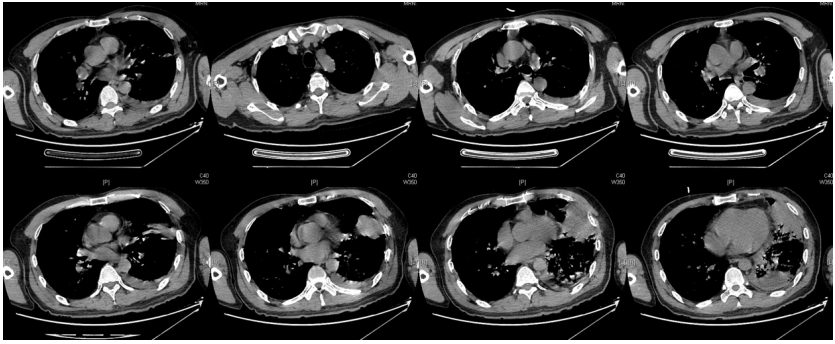

由于厌氧菌培养非常困难,既往我们对厌氧菌的认知仅限于在消化道定植,对其致病机制以及何种情况下致病并不非常清楚。厌氧菌定植于皮肤黏膜,是一种内源性微生物,感染发生率高,可导致严重、致死性感染。由于标本采集和转运的特殊性,使厌氧菌难以分离;加之其培养困难,体外生长慢,所以既往很难识别。厌氧菌在治疗方面存在一定挑战,如往往混合多重感染,且易产生耐药,也会因治疗延迟导致治疗失败。随着近10年来NGS技术的应用和普及,我们对厌氧菌的认识得以提升。常见的致病厌氧菌分为革兰阳性球菌、革兰阴性球菌、革兰阳性非芽孢杆菌、革兰阳性芽孢杆菌以及革兰阴性杆菌(表1)。革兰阳性非芽孢杆菌中可能致病的是放线菌,例如龋齿放线菌参与龋齿的发病过程。革兰阳性芽孢杆菌往往具有致病性,其中产气荚膜杆菌、艰难梭菌/难辨梭状芽孢杆菌、肉毒杆菌/肉毒梭菌、破伤风梭菌/杆菌具有强致病性。革兰阴性杆菌中的拟杆菌属对青霉素类药物具有很强的耐药性,易致青霉素治疗失败。临床中我们与厌氧菌的接触逐渐增多,对其特点也会愈发熟悉,对于临床诊断和治疗也会有所帮助。在NGS报告中通常会将检出的厌氧菌列为“C类”,定义为致病性C类—呼吸道正常微生态菌群,一般不导致感染。但当患者存在误吸风险时,需关注厌氧菌引起肺脓肿的可能。此时就需要针对患者的危险因素、临床表现、影像学、病原学以及气管镜下特点等进行综合分析。微小单胞菌最早是通过培养进行鉴定。瑞士2015—2022年132例病例报告的培养鉴定结果显示,血液中检出微小单胞菌37例(28%),肺内(肺脓肿、脓胸)检出29例(22%),总体病死率较低(5.3%)。国内周华教授团队开展的一项回顾性研究分析了2019年1月至2020年7月经病理活检和mNGS诊断的5例与微小单胞菌相关的慢性肺脓肿患者。患者的平均病程为6.5个月,共同特征是口腔卫生差,有酗酒史,且CT表现为边界不规则的高密度团块状实变影,并且在病灶中间可见液化性坏死,但没有发现气液平面或空腔,所以前期易被误诊为肺癌。下图1是该研究报告中病例3的肺部CT表现。时间点1:首次就诊时,左下叶可见团块状肺不张,伴周围磨玻璃样渗出病变,中心坏死不明显,可见细小空气囊泡影。时间点2:发病8个月时,可见大面积肺实变,增强CT示病灶内有液化坏死和小空洞。时间点3:经过3个月的有效抗厌氧菌治疗,病灶明显缩小,遗留空洞和纤维增殖病灶。图2是病例4的肺部CT表现。时间点1:患者首次就诊时,右上叶可见肿块样肺部实变影。时间点2:发病8个月时增强CT,可见实变明显增大,病灶内出现液化坏死。时间点3:经过3个月的有效治疗,病灶明显缩小,有残留空洞和纤维瘢痕样病变。由于通过影像学鉴别该病与肺癌具有挑战性,所以5例患者都接受了支气管镜检查和CT引导下经皮肺活检。5例患者经组织活检或支气管肺泡灌洗液(BALF)标本mNGS检测到微小单胞菌。病例: 女性, 67岁, 主诉"咳嗽咳痰2个月"。现病史:2个月前,患者家属感染新冠病毒(家属新冠抗原阳性)之后,患者出现咳嗽咳黄脓痰,无痰中带血及痰液拉丝,痰无臭味,无胸闷气短及胸痛,无咽痛咽痒,无鼻塞流涕。6月9日于当地市医院住院,住院期间出现发热,体温最高38.6℃,无寒战,查新冠病毒核酸阳性,予先诺特韦/利托那韦片口服治疗。查胸部CT见左肺上叶软组织影,左肺上叶炎症。诊断肺脓肿,予头孢唑肟联合莫西沙星,治疗后复查胸部CT(6月26日)病灶较6月9日明显吸收好转。6月14日气管镜检査见左肺上叶支气管开口狭窄,见大量脓性痰液堵塞支气管开口(病原学结果家属无法提供)。6月30日办理出院后仍有咳黄脓痰,无发热畏寒,口服止咳化痰药物,未使用抗生素。7月30日复诊胸部CT见左肺上叶异常密度较前增大。8月2日再次于当地市人民医院住院。8月4日气管镜检查: 左肺上叶黏膜肿胀肥厚, 管腔狭窄, 见大量白色干酪样分泌物涌出, 支气管镜不能进入。内科予莫西沙星静滴治疗10天, 外科予莫西沙星联合哌拉西林他唑巴坦静滴9天。复查胸部CT见病灶较前进展, 且右肺出现新发感染病灶。病程中患者饮食可, 睡眠差, 二便正常, 体重减轻5 kg。既往对阿莫西林过敏, 表现为口服阿莫西林后全身皮疹。否认嗜酒史及吸烟史。入院后胸部增强CT可见病灶内液化坏死,同时伴有小的空气囊泡影(图3)。患者有胸痛症状。气管镜检查发现气道内有痰栓或黏液栓阻塞征象(图4)。灌洗液tNGS结果回示:微小单胞菌(序列数2762),巨细胞病毒(序列数171),副流感病毒(序列数79),EB病毒(序列数61)。考虑病毒不会导致气道内如此改变,但由于微小单胞菌属于常见口腔定植菌,此时也不能完全确定微小单胞菌是否为引起感染的主要责任病原体。8月24日起予莫西沙星0.4 g qd ivgtt+哌拉西林他唑巴坦4.5 g q8h ivgtt。经过上述治疗,患者局部病灶有所吸收,但整个肺叶并无明显改善(图5)。气管镜检查仍然发现气道内有较黏稠的黏液栓阻塞气道开口(图6)。治疗经过:气管镜下予以局部冲洗,再次送检tNGS。9月7日结果回示:微小单胞菌(序列数6464),较前明显增多;副流感病毒(序列数998),EB病毒(序列数331)。9月9日起调整治疗方案为美罗培南1 g q8h。9月12日复查患者胸部CT,可见肺通气部分改善,肺组织内实变较前吸收(图7)。第三次气管镜检查仍可见少量痰栓嵌塞在远端支气管开口(图8)。患者此后转入医联体医院继续抗感染治疗。病例2:女性,54岁。主诉:咳嗽咳痰2个月,发热1周。现病史:入院2个月前,患者在西南地区旅游时感冒,出现咳嗽咳痰,白痰为主,量多,无胸痛,无发热,无痰中带血,咳时气短。于河北某诊所间断输液治疗14天(具体不详),期间口服中药治疗,症状未缓解。入院3周前(2023-09-07)就诊于当地县医院,查胸部CT提示右肺炎症,静脉滴注氨曲南、左氧氟沙星、氨溴索治疗1周,症状未缓解。2023年9月14日复查胸部CT显示右肺炎症较前加重,于当地中心医院住院。动脉血气分析:pH 7.43,PaCO2 38.4 mmHg,PaO2 67 mmHg,SaO2 94.2%;血沉90 mm/h;生化:白蛋白35.3 g/L;CRP 82.7 mg/L;血常规:WBC 9.75×109/L,NEU 6.83×109/L,HGB 104 g/L。静脉滴注莫西沙星。入院10天前,行肺穿刺活检,病理回报为少量肺组织及纤维结缔组织,炭末沉积,较多中性白粒细胞、淋巴细胞及浆细胞浸润,伴脓肿形成;肺穿刺mNGS结果回报:微小单孢菌(序列数2650),鲍曼不动杆菌(序列数17),人类疱疹病毒4型(序列数60),人类疱疹病毒7型(序列数5),文氏密螺旋体(序列数4337),解卵磷脂密螺旋体(序列数1121),齿垢密螺旋体(序列数698)。调整抗生素为头孢哌酮舒巴坦2 g q12h。入院1周前,出现发热,体温最高38.5℃,不伴寒战,咳嗽咳痰无加重,无咯血;复查血常规、PCT、CRP均明显增高(未见报告单);复查胸部X线提示右肺炎症范围增大,右侧胸腔积液。更换抗生素为哌拉西林他唑巴坦4.5 g q8h。4天前,支气管镜下见右肺下叶背段支气管略狭窄,黏膜水肿,可见脓性分泌物溢出。BALF革兰染色查见革兰阴性杆菌,抗酸染色、霉菌未见异常,培养未回报。患者体温逐渐降至正常,咳嗽咳痰有所减轻,复查胸部CT提示右肺高密度影,右侧胸腔积液较前增多。为求进一步诊治来我院就诊被收入院。既往甲状腺功能减退病史5年,目前口服优甲乐治疗,监测甲状腺功能指标在正常范围。20年前因宫外孕行手术治疗。2023年10月8日胸部CT示胸膜下斑片状坏死,纵隔窗可见微小空气囊泡影及密度不均匀液化坏死(图9)。治疗:9月28日至10月13日莫西沙星0.4 g qd ivgtt+哌拉西林他唑巴坦钠4.5 g q8h ivgtt。最终患者病灶吸收好转并顺利出院。患者男性,42岁。主因间断咳嗽、咳痰1月余,左侧胸痛、气短2天入院。现病史:入院前1月余(2022-07-19),患者无明显诱因出现咳嗽,咳白痰,痰中有少量鲜红色血丝,左侧胸痛(为钝痛),深吸气后加重,就诊于当地医院。完善肺动脉CTPA:示左上肺动脉舌段分支局部管腔可见线条样低密度充盈缺损,考虑肺栓塞;左肺上叶实性病变伴不均匀强化,性质待定,部分为肺梗死改变可能,纵隔多发稍大淋巴结,性质待定;右肺下叶后基底段可见一不规则实性结节,边缘可见多发毛刺,直径约0.7 cm。当地医院考虑肺栓塞不除外,肺部感染?右肺下叶结节,予莫西沙星抗感染,低分子肝素抗凝,乙酰半胱氨酸化痰。完善CT引导下肺穿刺活检,病理示:肺泡腔扩张伴上皮轻度增生,肺泡间隔纤维组织增生伴散在炎细胞浸润,未见恶性病变。院外规律应用甲磺酸艾多沙班60 mg bid抗凝,先后间断应用左氧氟沙星0.5 g qd、头孢类抗生素(具体药物、剂量不详)抗感染。患者仍有间渐咳黄白痰,量不多,痰中有少量鲜红色血丝;无畏寒、发热、胸痛、夜间阵发性呼吸困难症状,无尿少、双下肢水肿,无口干、咽干,无牙齿成片脱落,无晨僵、关节肿痛,周身无皮疹,无盗汗乏力。2天前(2022-09-16)患者无明显诱因再次出现左侧胸痛,疼痛剧烈,深吸气、咳嗽及改变体位时加重,伴气短,就诊于我院急诊。完善肺动脉CTPA:肺动脉主干及其各叶段分支未见明显充盈缺损,左肺上叶舌段团块影,最大截面约7.6 cm×5.3 cm,边界不清,周围可见晕征;增强扫描不均匀强化,邻近胸膜增厚,性质待定,建议穿刺活检;纵隔及左肺门多发淋巴结显影。血细胞分析:WBC 11.09×109/L,NEU% 80.8%,NEU 8.95×109/L;CRP 54 mg/L,PCT 0.07 ng/ml。患者自发病以来,精神状、食欲及睡眠均一般,大小便正常,体重下降5 kg。2022年9月14日外院胸部增强CT:胸膜下楔形的影像学表现可见少量小气泡囊以及液化坏死病灶(图10)。初始考虑肺部肿瘤及肺栓塞。经过初步抗感染及抗凝治疗,患者病情无缓解,2022年9月27日患者突发胸痛,下肺影像加重并且出现脓胸(图11)。行胸腔穿刺并将脓液送检mNGS,结果回报:牙龈卟啉单胞菌(序列数3)。尽管序列数很低,但考虑是脓肿穿刺结果,因此考虑该菌致病可能。抗厌氧菌治疗:9月16-28日莫西沙星0.4 g qd ivgtt,9月23日-10月12日美罗培南1 g q12h ivgtt,9月28日-10月8日万古霉素1 g q12h ivgtt,10月13-18日莫西沙星0.4 g qd ivgtt+甲硝唑0.5 g tid ivgtt。患者肺脓肿的整体治疗时间约为3个月,病灶逐渐吸收,最终形成一些纤维索条影(图12,图13)。1年后复查病灶基本吸收(图14)。图14 1年后复查胸部CT(2023-08-08)微小单胞菌和卟啉单胞菌这两种厌氧菌在临床中需要引起重视,它们容易引起肺脓肿/脓胸。2024年国内学者Li Yao等在Diagn Microbiol Infect Dis 杂志发表了一篇牙髓卟啉单胞菌感染所致肺脓肿的病例报告,文章也提到在胸水或肺组织活检中,通过mNGS同时检出了微小单胞菌和卟啉单胞菌感染引起的肺脓肿。文章还回顾总结了既往发表的厌氧菌感染引起肺脓肿的病例,2010年报道的是1例脑脓肿患者,2019年报道1例脑炎患者,2022年报道1例脓胸伴呼吸衰竭患者。3例患者预后都比较好,可见厌氧菌亦可导致肺外多部位感染。对于厌氧菌所致肺脓肿的诊断及其引起的脓胸,目前的文献报道仍然较少,我们对它们的认知也有限,因此也提醒大家关注相关疾病的诊断和治疗。我们也已将本研究小组8例微小单胞菌所致肺脓肿的系列病例的研究结果发表(Front Cell Infect Microbiol, 2024, 14: 1416884),可供需要的同行参考。对于厌氧菌感染,我们需要提高警惕。厌氧菌往往在口咽部定植,其引起的脓肿/感染往往多为亚急性或慢性起病。患者通常有发热、胸痛症状,脓肿会逐渐进展。由于厌氧菌与人体本身是一种长期共生的关系,人体对厌氧菌的免疫识别可能处于较低的防御反应状态,所以会形成一个亚急性或慢性的发病过程。通常情况下,因厌氧菌的菌群发生了移位,从卫生条件不好的口腔扩展到相对无菌的肺内,同时开始增殖,由此可能导致感染。因此,对于酗酒以及口腔卫生非常差的人群,我们要重视对其风险因素和病史的排查。患者就诊时可能病情并不重,有胸痛或咯血,很容易误诊为肺部肿瘤,往往在这种情况下进行肺穿刺或气管镜检查,mNGS可以发现较大序列数的厌氧菌。但在mNGS检出厌氧菌后的诊断过程中又容易形成误判——究竟是致病菌,还是定植菌?此时结合患者其他病史和影像学特点(有脓肿/痰栓形成,微小空气气囊泡影),可能提示厌氧菌感染。然而,厌氧菌感染在病原学和影像学诊断方面仍然存在诸多困难,极易漏诊和误诊。微小单胞菌感染患者在气管镜下可以看到典型的脓性分泌物嵌塞气道,导致气道阻塞,也会造成远端气道和肺泡引流障碍。所以,及时处理气道内痰栓,改善引流,可能是使患者获得良好预后的关键。厌氧菌肺脓肿的吸收比较缓慢,抗感染的疗程也比较长,需要在后期诊疗过程中密切随访和观察患者对治疗的反应以及耐药等问题,及时调整治疗方案,适当延长疗程。